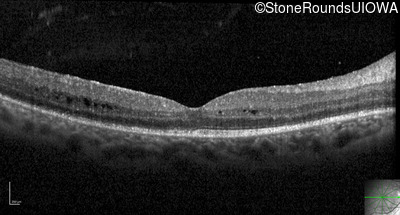

Optical Coherence Tomography - Right - 20/32 -1

Exemplar / OCT Stack